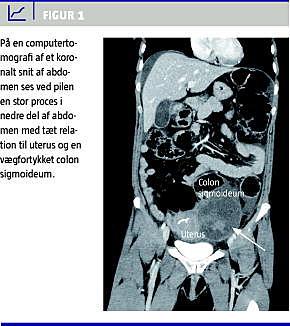

En computertomografi (CT) af abdomen foretaget med intravenøst kontrastmiddel viste fri væske, ødematøs og vægfortykket colon sigmoideum med afsmalning af lumen over ca. 20 cm, en 9 × 8 × 8 cm proces i venstre fossa iliaca i nær relation til ovariet og tre små fokale forandringer i leveren (Figur 1 ).